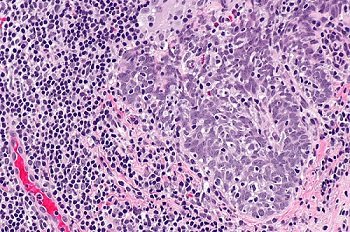

病毒入侵也會導致細胞或組織發生病理變化,如感染細胞與未感染細胞的胞漿膜發生融合,形成多核的巨細胞,或某些病毒感染細胞時,在光學明場顯微鏡下可見胞漿或胞核內出現嗜酸或嗜堿性染色、大小不同和數量不等的圓形或不規則的團塊結構,如HPV人乳頭狀瘤病毒。

HPV引起,分化不良的鱗狀細胞癌